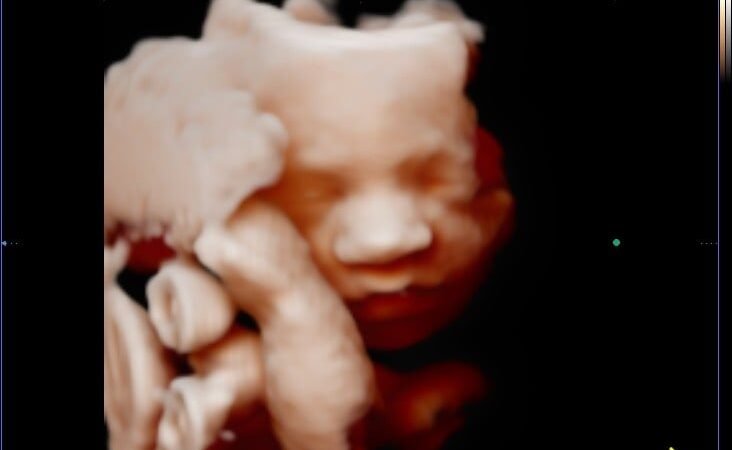

La ecografía 5D es la tecnología más avanzada disponible hoy en día. Mantiene el movimiento en tiempo real de la 4D, pero da un salto enorme en calidad de imagen: mayor nitidez, resolución superior, colores y tonalidades de piel más naturales y un efecto hiperrealista que hace que la imagen parezca casi una fotografía real del bebé.

Con la ecografía 5D puedes distinguir perfectamente los rasgos faciales de tu bebé: si tiene los labios de papá, la nariz de mamá, o esa expresión tan característica que ya os está regalando desde el vientre.